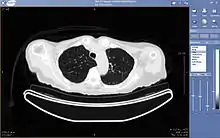

A CT exam displayed through teleradiology

Teleradiology is the ability to send radiographic images (x-rays, CT, MR, PET/CT, SPECT/CT, MG, US...) from one location to another.[76] For this process to be implemented, three essential components are required, an image sending station, a transmission network, and a receiving-image review station. The most typical implementation are two computers connected via the Internet. The computer at the receiving end will need to have a high-quality display screen that has been tested and cleared for clinical purposes. Sometimes the receiving computer will have a printer so that images can be printed for convenience.